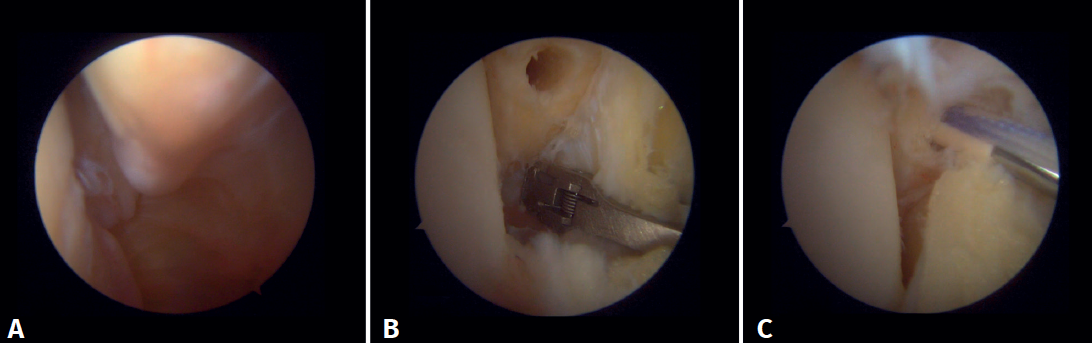

Arthroscopic evaluation of the syndesmosis

From the anteromedial portal we can directly visualize the distal fibers of the ATFL. Disinsertion of these fibers does not always result in instability of the syndesmosis, but it does require us to check it. In our experience, we prefer assessment of the coronal plane of the syndesmosis. We introduce the arthroscope into the tibiotalar joint directing the camera cranially. In this way we have a direct view of the distal tibiofibular joint. We then assess stability by attempting to insert the palpation probe into the joint. If it is possible to do so, we classify the syndesmosis injury as unstable (Figure 6A).

Surgical technique: arthroscopic treatment of acute syndesmosis injuries

The technique should be performed using the conventional anteromedial and anterolateral portals. The anteromedial portal is used for visualization, while the anterolateral portal serves as the working portal. Once the tibiofibular space is visualized, the inflamed synovial component is resected with an arthroscopic shaver to facilitate reduction (Figure 7A). Then, under direct vision, we restore the tibiofibular space, carefully taking into account possible malrotation of the fibula, especially in Maisonneuve type fractures. For fibular reduction we use a Verbrugge clamp, which allows us to correct the rotation. In our experience, once the space has been cleaned and if the position is correct, it is infrequent to have to use a compression clamp between the tibia and fibula.

Once the desired reduction has been achieved, we visually check the position and temporarily fix it using a Kirschner pin.

For definitive fixation, the surgical options range between rigid fixation with screws and dynamic fixation. Screws have been the standard procedure for decades, but involve complications, such as loosening or rupture. Furthermore, some surgeons advocate their removal, with the inherent risk of recurrence of instability(27). Dynamic fixation was designed to overcome some of these problems by allowing a degree of physiological movement of the syndesmosis, facilitating early weight bearing, reducing the risk of rupture, and eliminating the need to remove the implant (Figure 7B).